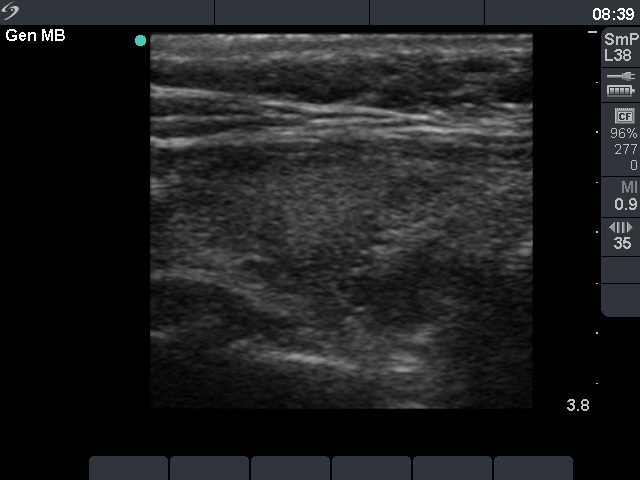

Right lobe, longitudinal scan

Right lobe, longitudinal scan. The moderately hypoechogenic lesions do not correspond to a nodule.